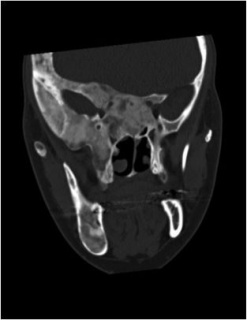

Fibrous dysplasia can resemble other entities including meningioma, Paget’s disease or other osteodystrophies of the skull base, eosinophilic granuloma, Hand-Schuller-Christian disease, and low-grade central osteosarcoma. [17][3][5] Unlike fibrous dysplasia, meningiomas will exhibit a homogenous, sclerotic appearance if hyperostosis is present (Figure 4), may involve surrounding soft tissue, and display rapid contrast enhancement on MRI. [11]

Figure 4. Meningioma initially diagnosed as fibrous dysplasia.